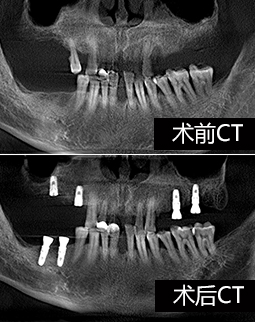

过去十天了,今天去拆线,然后歇上一段时间,我的手术创口比较多,难免要缝合。种植体重新拍摄了CT,植入良好,医生今天给我检查,种植牙术后并没有肿胀,恢复的还算不错,看来我老骥伏枥,体质还不错,也感谢医生种牙技术的高超,种植体都是微创的手术,种植牙的创口减小了,种植牙术后就更容易恢复了。

我听过的拒诊理由很多,有“年纪太大了,怕风险高”,“你这骨量不好,种牙难度太大了”,“缺牙数太多,难度也大,可以做但是很贵,你还是换其他方法吧”,在这里我看到了希望…医生技术好,还会为我省钱,给过做种植体+冠桥,缺了8颗大牙,种6颗种植体就够了。

面对我参差不齐的骨量,整个团队都围绕着我想方案,最终确定了给我骨粉骨膜搭配植骨的方式重新夯实我的骨量,老爷子我很感恩。

老爷子我做种植牙的费用明细想公开一下,我长期缺牙所以骨量都萎缩了,所以选了比较好的种植体,费用是六个种植体和基台,加上八颗全瓷牙冠,植骨手术和骨粉骨膜的费用另外算。所以呢,年轻人啊,缺牙了就赶紧去种牙吧,别选不合适的镶牙方法,年纪轻轻呢,后半辈子比我更精彩,何必搭上剩下健康牙齿的幸福?种植牙和镶牙之间,你们还是种牙吧。